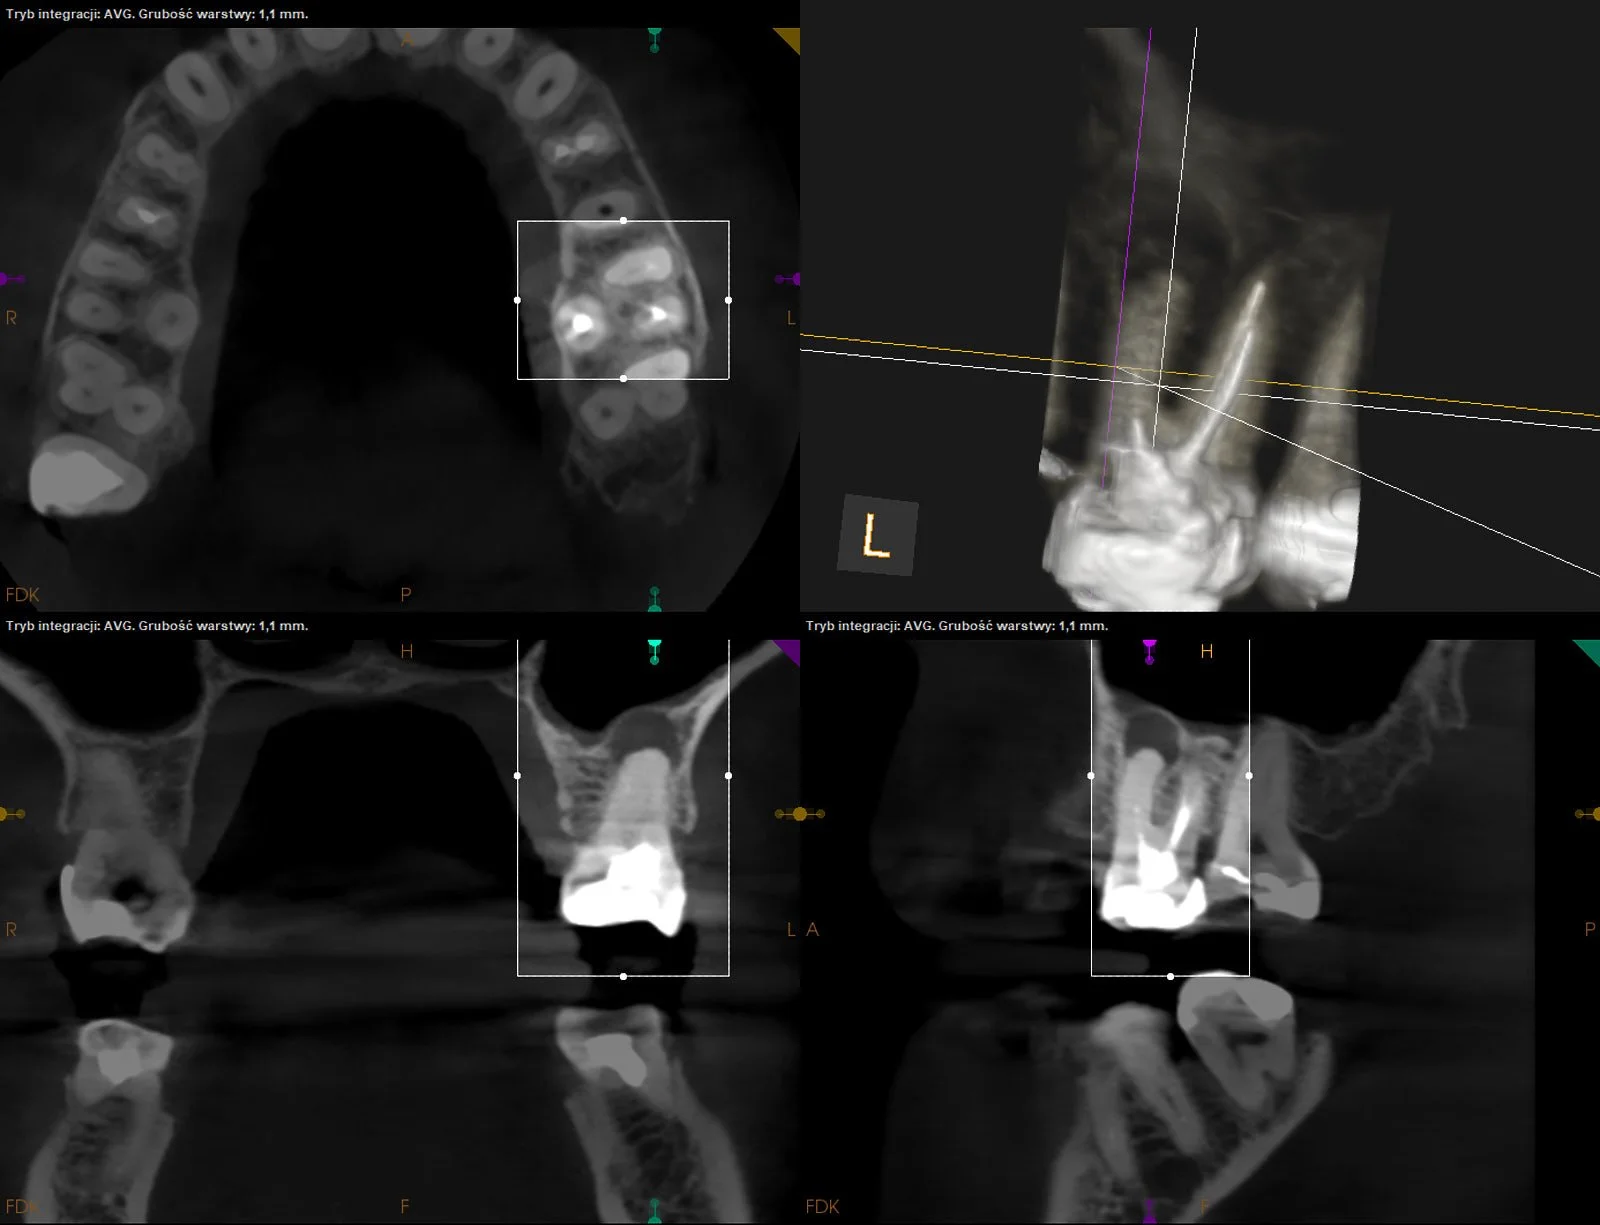

Usunięcie ankera zacementowanego na cement kompozytowy oraz reendo d.45 wraz z wykonaniem odbudowy adhezyjnej.